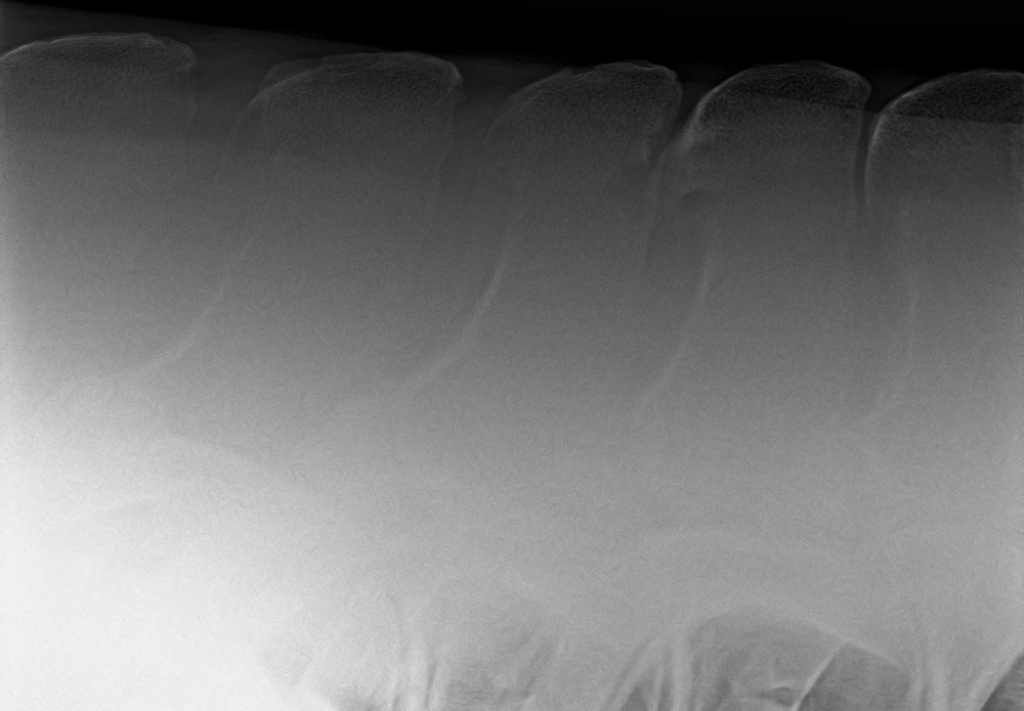

Links: Röntgenopname met daarop botverdichting en botoplossing van de borstwervels

Rechts: Röntgenopname met vormveranderingen van de doornuitsteeksels met daarbij ook botoplossing

Röntgenopname met daarop botverdichting en botoplossing van de borstwervels

Röntgenopname met vormveranderingen van de doornuitsteeksels met daarbij ook botoplossing

Als blijkt dat het om een primair rugprobleem gaat dan is de volgende stap om röntgenopnames van de rug te maken. Op röntgenopnames zijn de doornuitsteeksels en eventuele afwijkingen goed te zien. Verder is het mogelijk om de facetgewrichten van de rug en het SI gewricht echografisch te onderzoeken als daar aanleiding toe is. Om te bevestigen dat de klachten worden veroorzaakt door de kissing spines kunnen we de regio rond de afwijkende doornuitsteeksels tijdelijk verdoven. Als het paard daarna minder klachten vertoont dan is dat een sterke aanwijzing dat de kissing spines de oorzaak (of onderdeel van de oorzaak) is van de klachten.